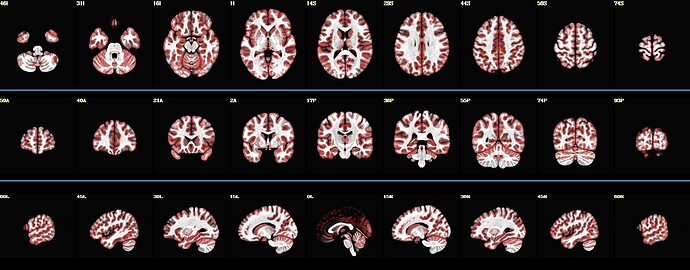

So far, code below can produce images like displayed below :

@chauffeur_afni \

-ulay ${background} \

-ulay_range "2%" "98%" \

-olay ${tempFolder}/meanInputDataSet+tlrc \

-func_range_perc_nz 1 \

-set_subbricks 0 0 0 \

-box_focus_slices ${tempFolder}/meanInputDataSet+tlrc \

-cbar "Reds_and_Blues_Inv" \

-pbar_saveim ${tempFolder}/color_bar \

-opacity 4 \

-prefix $tempFolder/tempPlots \

-thr_olay 0 \

-save_ftype JPEG \

-montx 9 -monty 1 \

-montgap 3 \

-set_xhairs OFF \

-pbar_posonly \

-label_mode 1 -label_size 3

colorbar_tool.py -in_cbar ${tempFolder}/color_bar.jpg \

-in_json ${tempFolder}/color_bar.json \

-prefix ${tempFolder}/test1.jpg

2dcat \

-gap 5 \

-gap_col 66 184 254 \

-nx 1 \

-ny 4 \

-prefix ${output_prefix} \

$tempFolder/tempPlots*jpg ${tempFolder}/test1.jpg